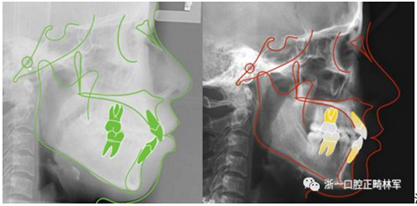

治療前后側(cè)位片對比

11.png

治療前后頭影測量重疊圖(綠色治療前,紅色治療后)

12.png

有了更柔和的側(cè)貌和更甜美的微笑,相信這個女生今后會更自信,人生會更精彩。

矯正不僅僅可以獲得整齊的牙齒,我們正畸醫(yī)生的目標是美觀、功能、穩(wěn)定、健康。站得更高、看的更遠,矯正改變?nèi)松?/p>